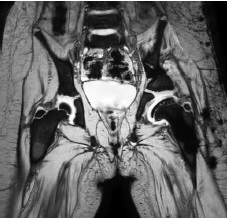

According to the MRI, all patients had deformity of the cartilaginous model of the proximal epiphysis of the femur and labrum acetabulum (Fig. 3). The latter, in our opinion, arose due to the forming coxa magna and hip subluxation.

Fig. 3. Magnetic resonance imaging of a patient, born in 2015, with the diagnosis of Perthes disease in the stage of fragmentation with total lesion of the femoral head (Catterall IV) and hip subluxation (explanations in the text)